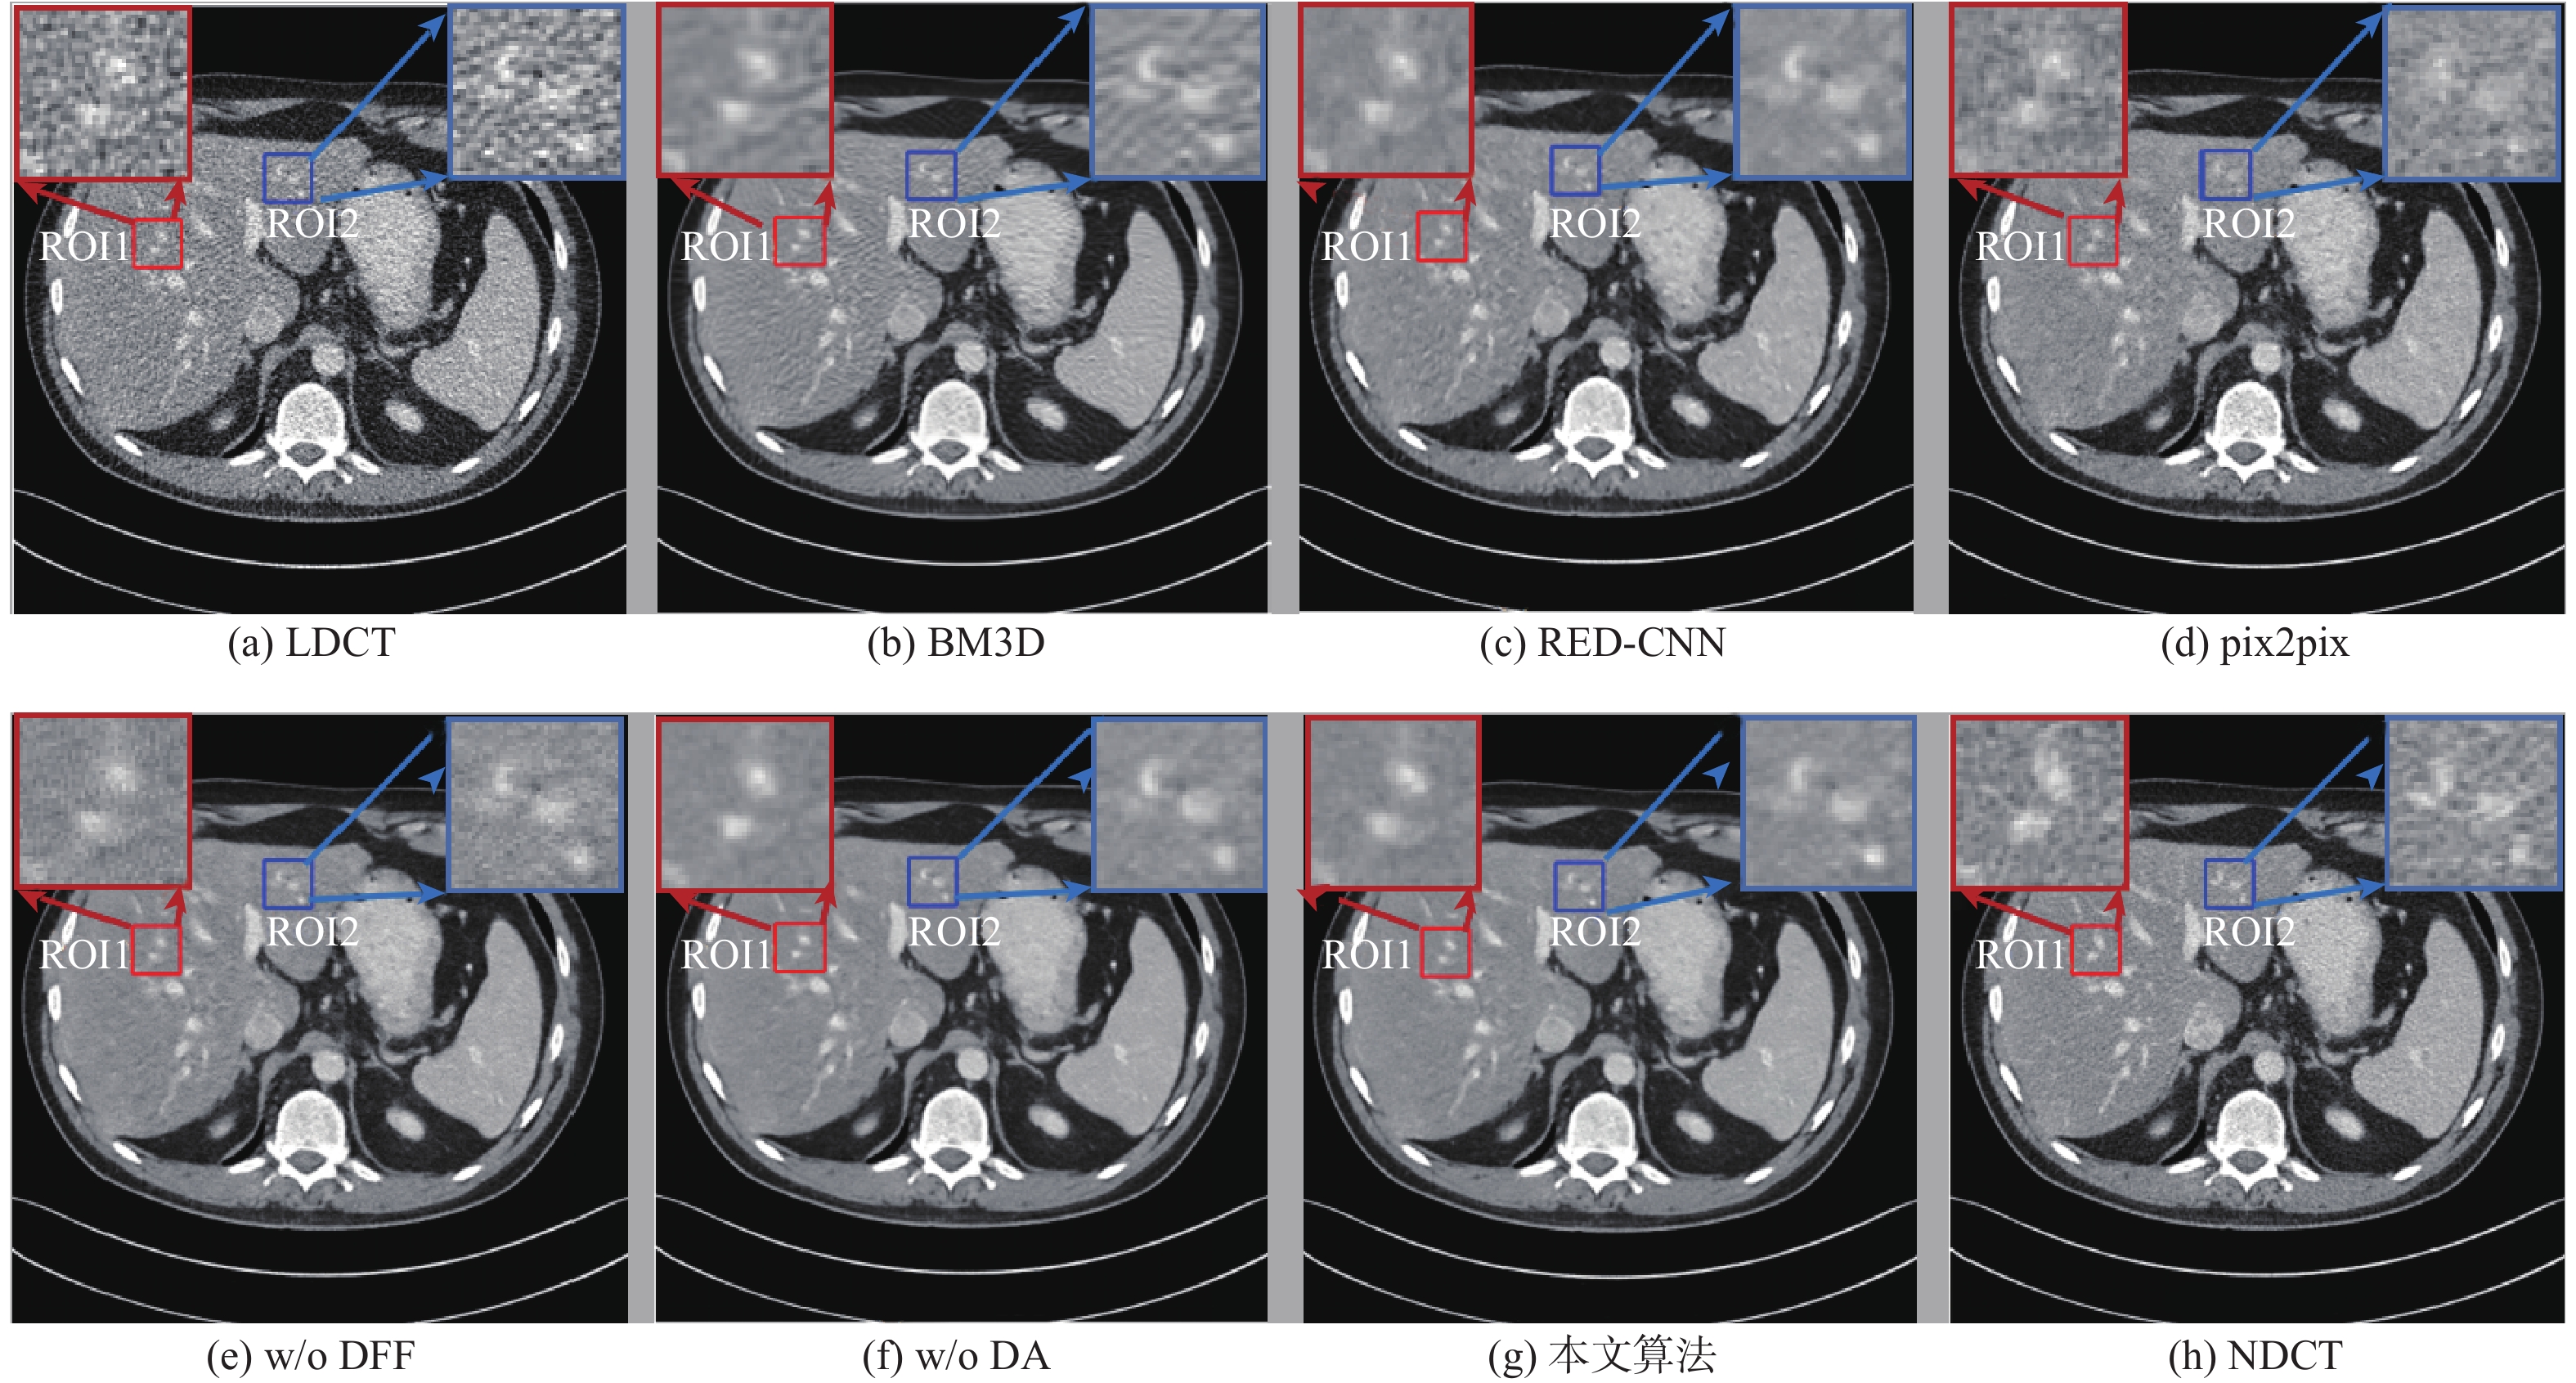

A low-dose CT image denoising method based on artifact estimation

HAN Xinglong, SHANGGUAN Hong, ZHANG Xiong, HAN Zefang, CUI Xueying, WANG Anhong

2023, 49(2): 491-502. doi: 10.13700/j.bh.1001-5965.2021.0263

Abstract:

Low-dose CT (LDCT) contains abundant tissue structure, pathological information and noise artifacts with extremely irregular distribution.These two different types of information have comparable amplitude distributions. Therefore, the LDCT denoising task is prone to some problems, such as insufficient feature extraction, insufficient network sensitivity to the directional characteristics of noise artifacts, and excessive smoothing of the denoising results. In response to the above problems, this work uses the U-Net network as the basic model of the denoising network, and designs a LDCT denoising network based on artifact estimation. The proposed network mainly includes two parts: the main feature extraction network and the direction-sensitive attention sub-network.Firstly, to better use the differences between various scale features and increase the efficiency of feature extraction, we add a dense feature improvement module to the codec U-Net structure. Secondly, we design a direction-sensitive attention subnetwork to improve the sensitivity of the denoising network to the direction characteristics of the noise artifacts. Finally, to ensure the stability of network training, we utilize a variety of loss functions to optimize the network training process. The experimental results show that the proposed algorithm is superior to other mainstream LDCT denoising algorithms in terms of visual effects and quantitative indicators.